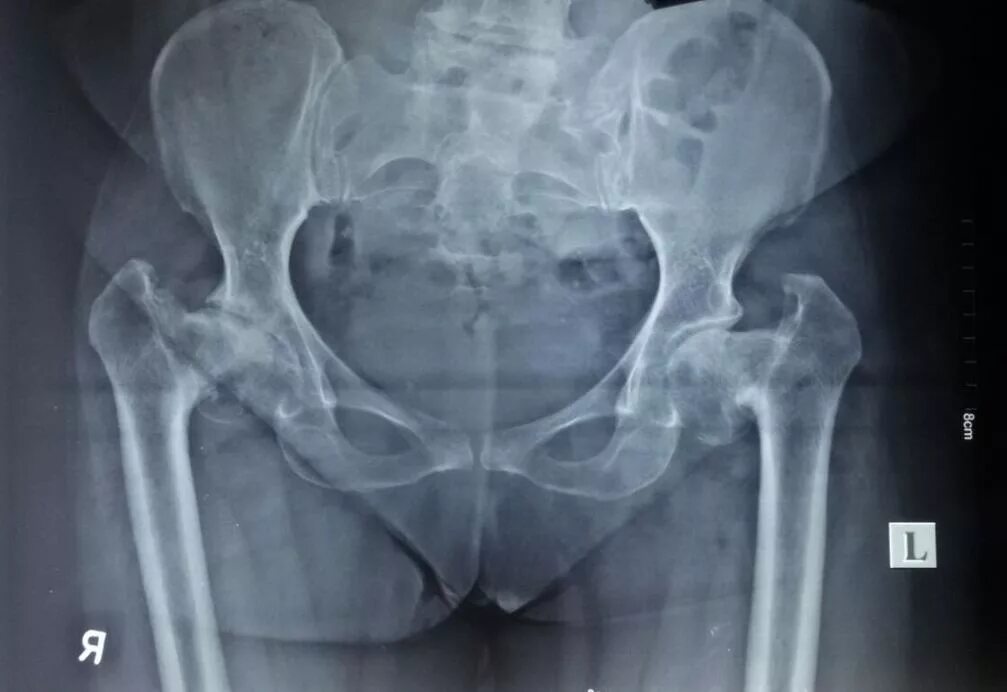

Деформация тазобедренного